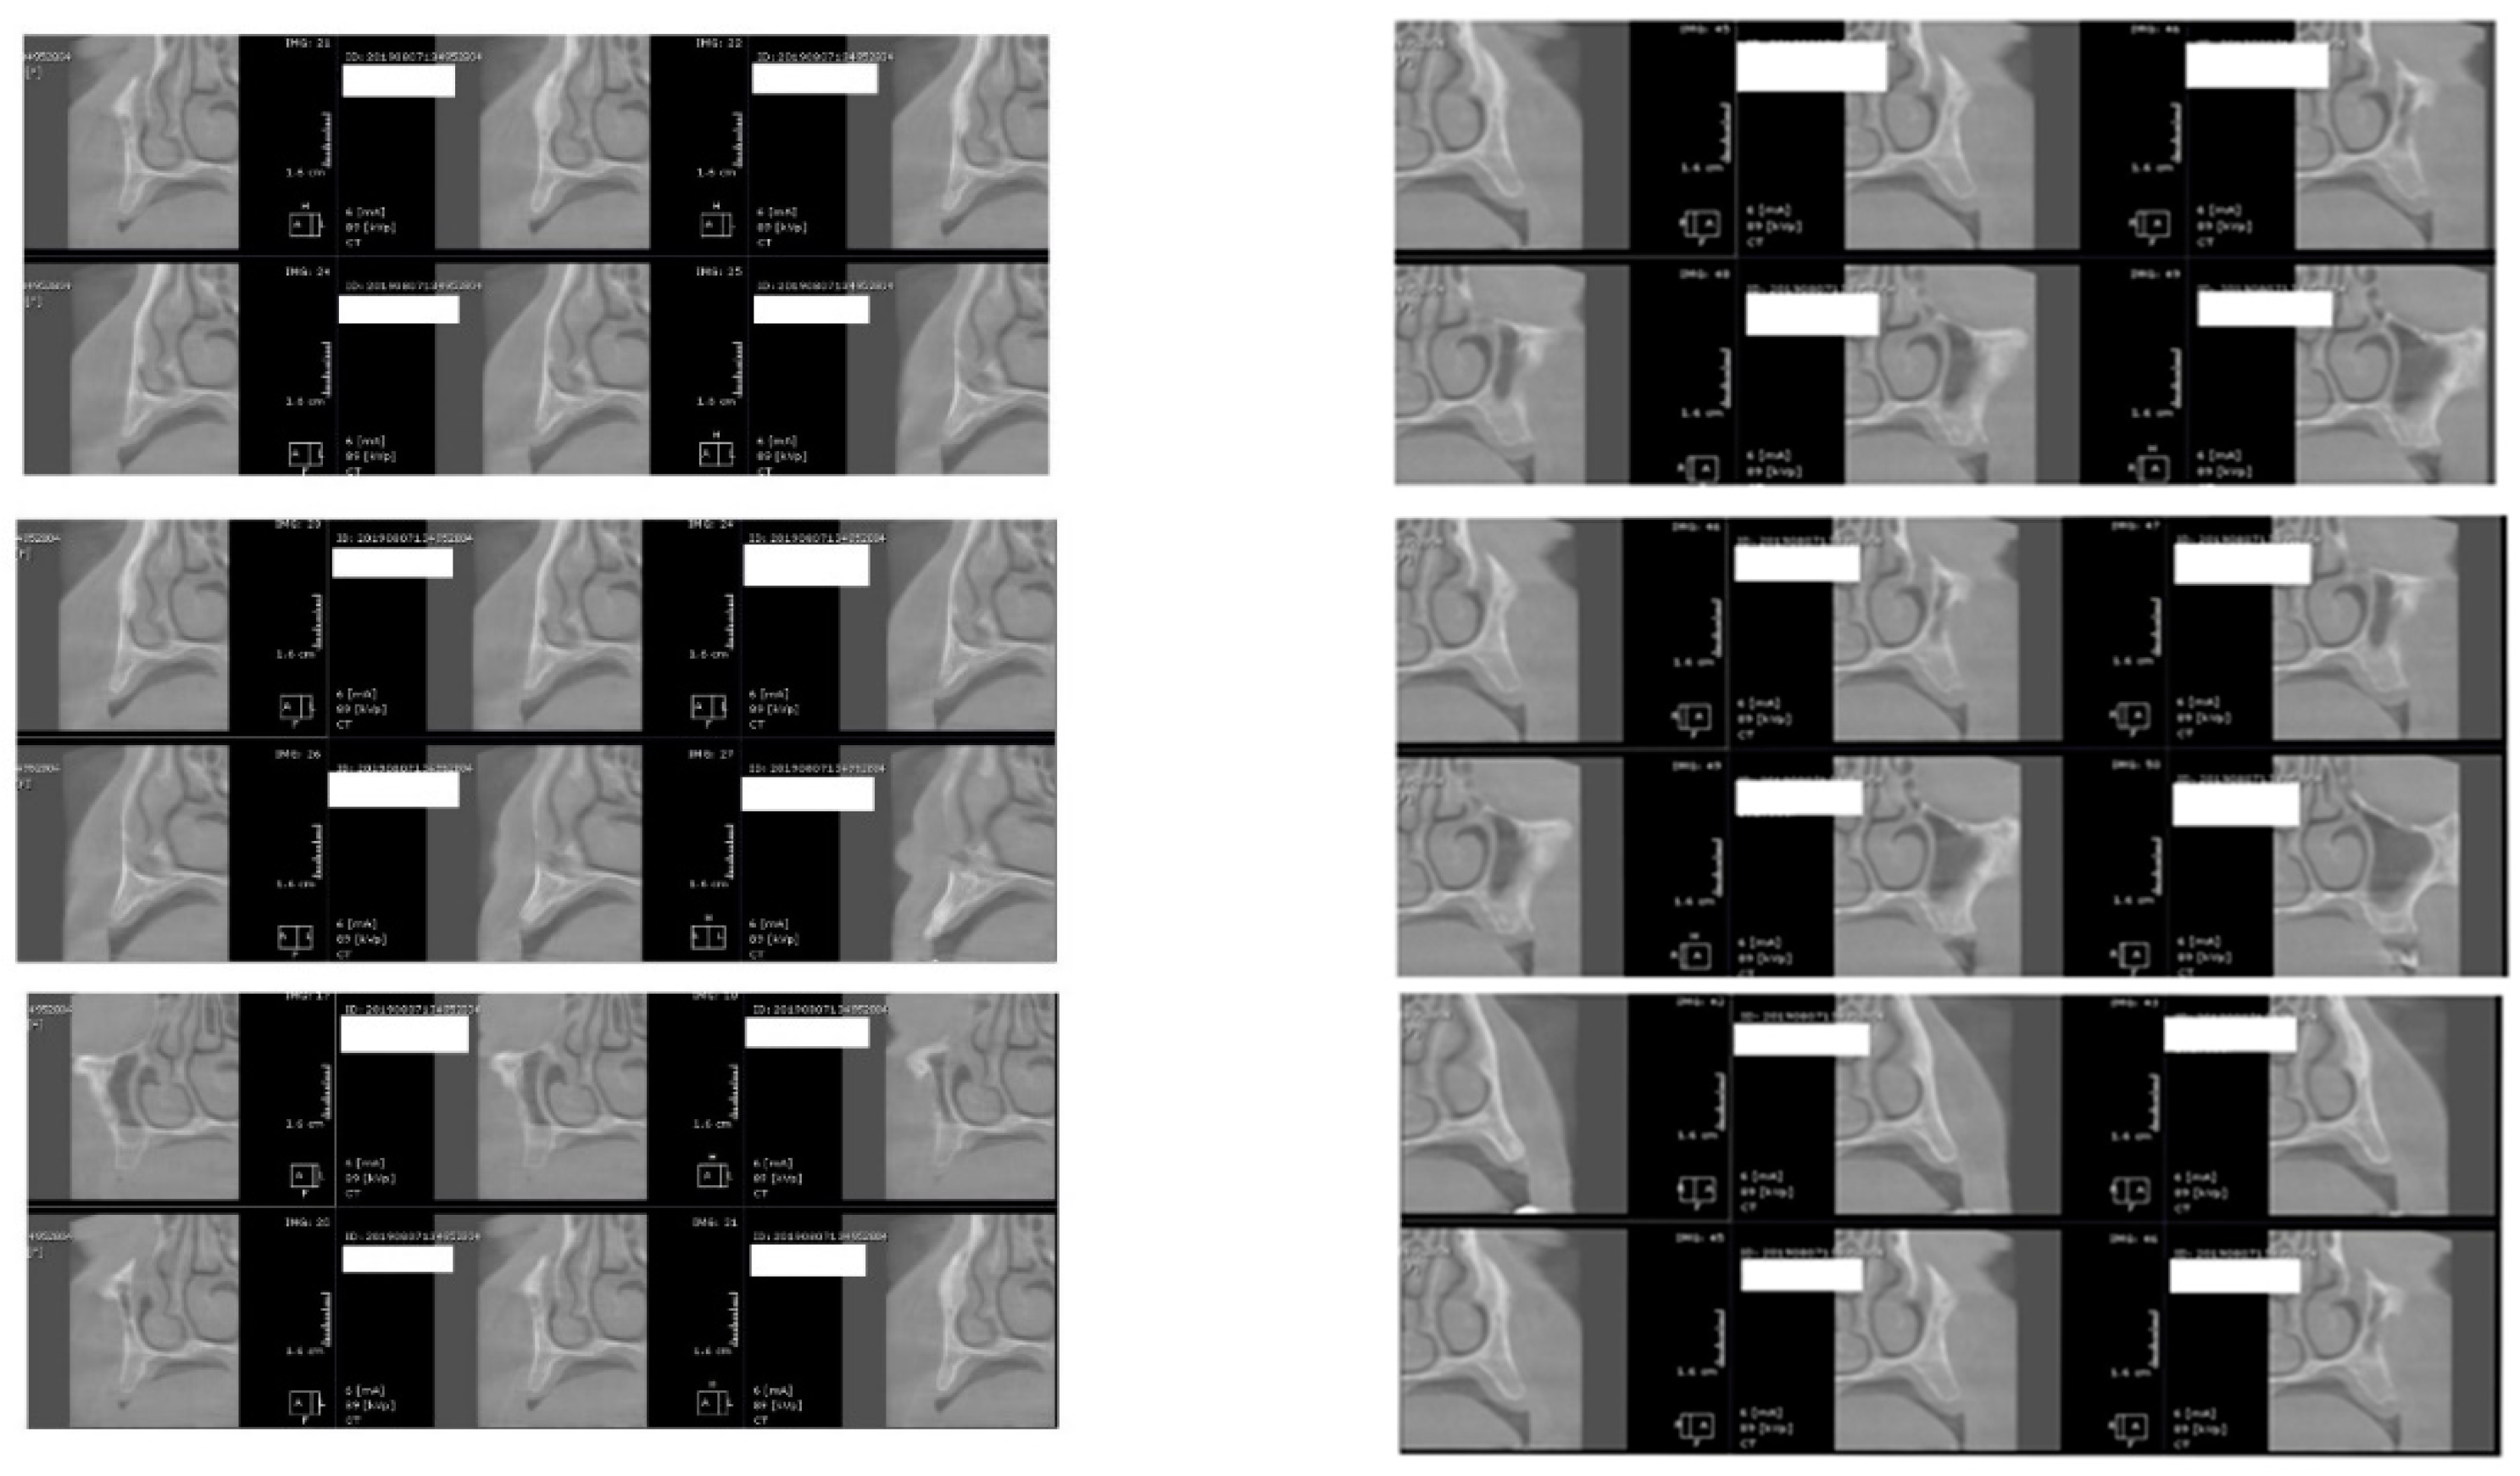

After 60 days of healing process, new CBCT images were recorded in order to assess bone density changes that might have occurred near the implant sites (Figure 9, Figure 10 and Figure 11).

Figure 9.

Random CBCT images with conventional healing caps in place.

Figure 10.

Random CBCT sections with pulse electromagnetic healing caps in position.

Figure 11.

Random CBCT images with pulse electromagnetic healing caps in position.

In the next phase of the study, after a healing period of 60 days, new measurements regarding bone density were recorded (Figure 12 and Figure 13). To avoid the metal artifact/beam hardening effect created by implants, new measurements were recorded at a 2 m distance from the implant site.

Figure 12.

Bone density around dental implants at 60 days following surgery with conventional healing caps.

Figure 13.

Bone density around dental implants at 60 following surgery with MED™ electromagnetic healing caps.